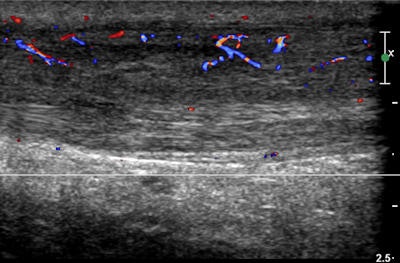

Ultrasound shows thickening of the left Achilles tendon in a 34-year-old man who is a triathlete. Neovascularity is in keeping with Achilles tendonitis. Image courtesy of Dr. Denis Remedios.To plan for future games, a critical analysis is required for diagnostic and interventional radiology needs, and this prompted Remedios and his colleagues to look at the similarities and differences between Baku and other major games with regard to three criteria: organization, clinical aspects, and the legacy of radiology services. They gathered data from Baku prospectively from the organizational stages and during the games time using a bespoke RIS-PACS (Distribution and Control Management, DCM).

- Hurdler with an inversion ankle injury. Color flow ultrasound showed a grade 2 partial tear of the anterior talofibular ligament.